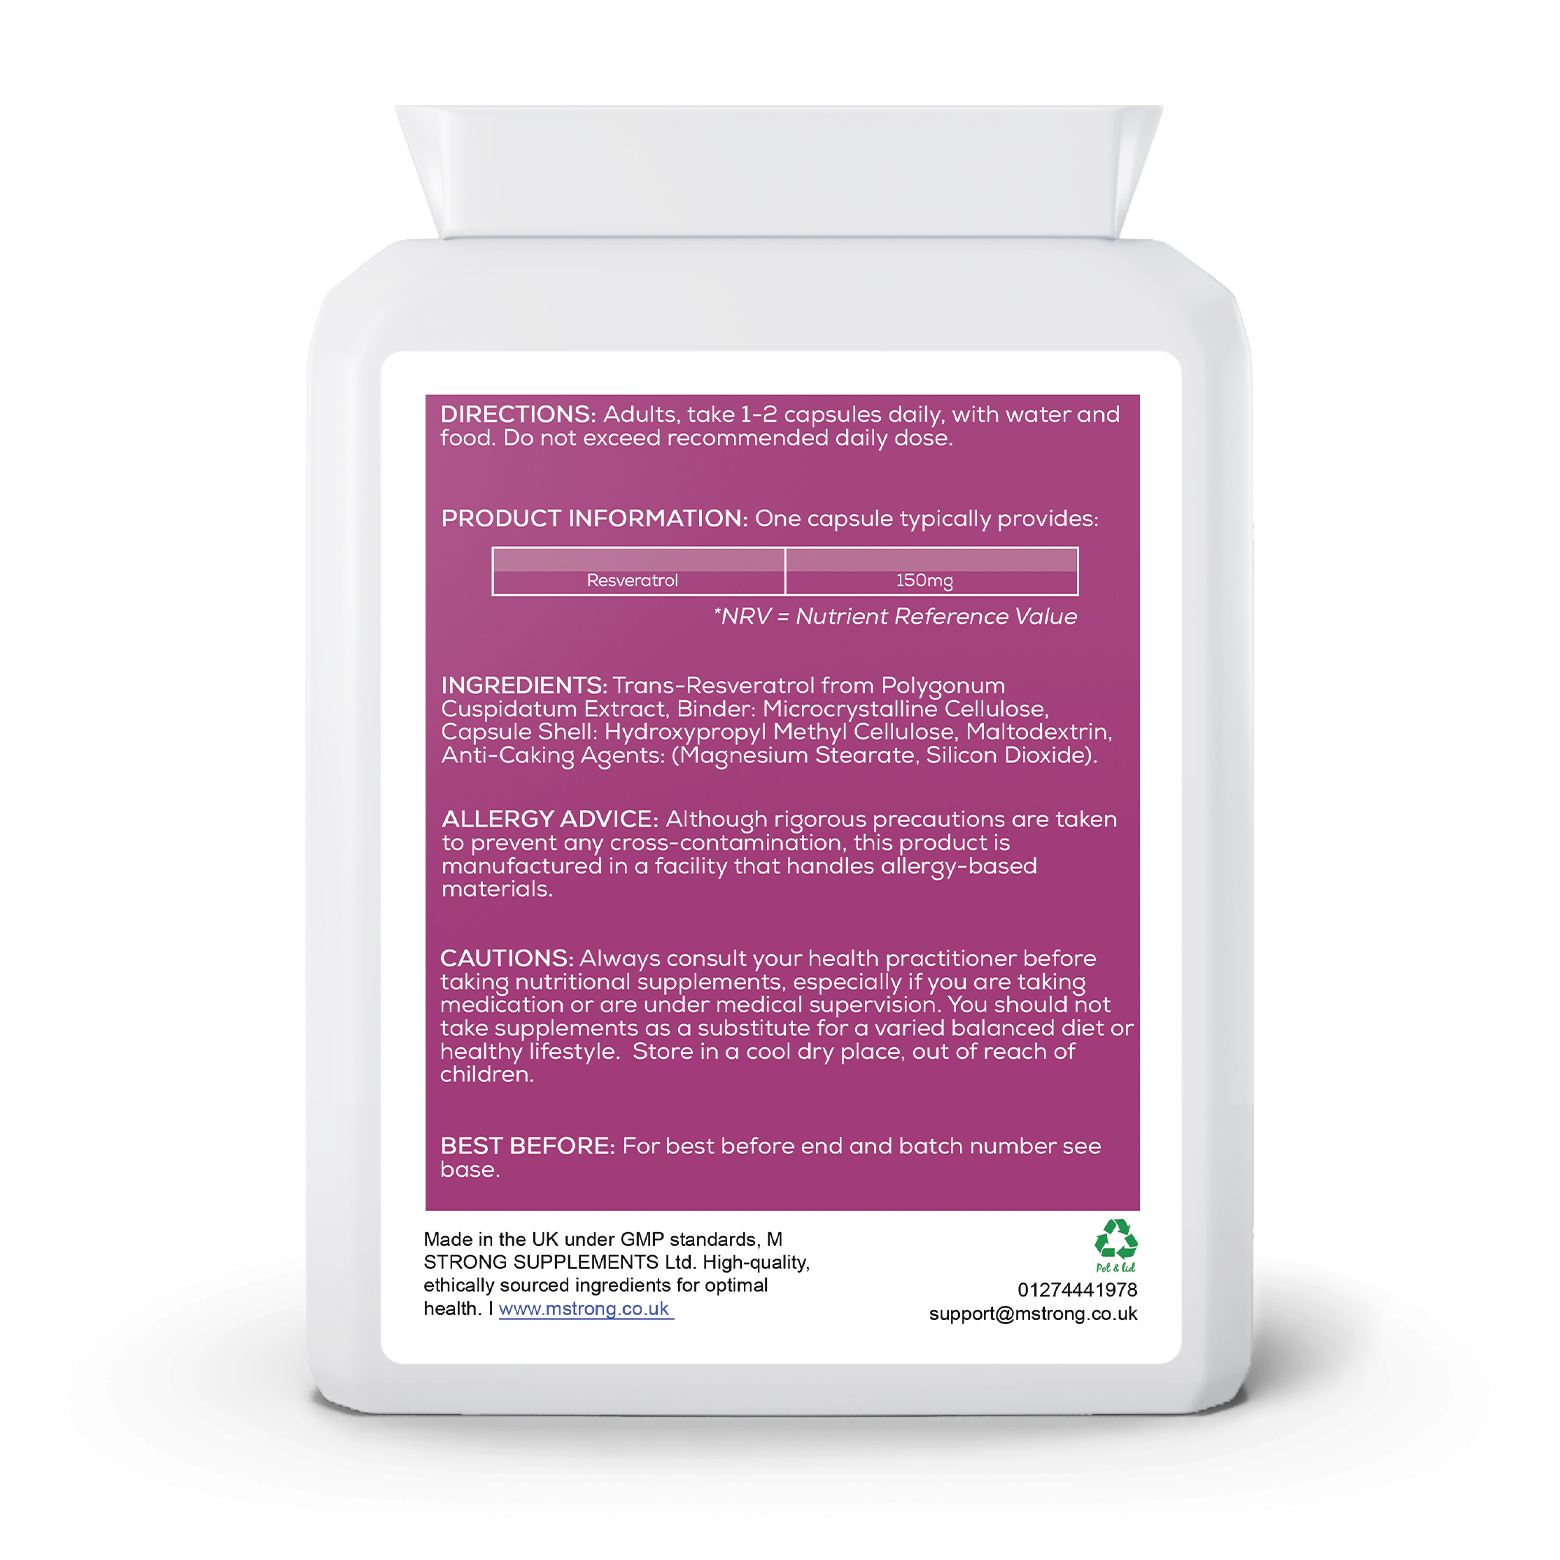

Adults, take 1-2 capsules daily, with water and food. Do not exceed recommended daily dose.

Ingredients

Trans-Resveratrol from Polygonum Cuspidatum Extract, Binder: Microcrystalline Cellulose, Capsule Shell: Hydroxypropyl Methyl Cellulose, Maltodextrin, Anti-Caking Agents: (Magnesium Stearate, Silicon Dioxide).

Allergy Advice

Although rigorous precautions are taken to prevent any cross-contamination, this product is manufactured in a facility that handles allergy-based materials.

Cautions

Always consult your health practitioner before taking nutritional supplements, especially if you are taking medication or are under medical supervision. You should not take supplements as a substitute for a varied balanced diet or healthy lifestyle. Store in a cool dry place, out of reach of children.

Storage

For best before end and batch number see base.